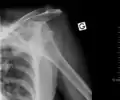

Anterior dislocation of the left shoulder.

A shoulder dislocation often occurs as a result of a fall onto an outstretched arm or onto the shoulder.[3] Diagnosis is typically based on symptoms and confirmed by X-rays.[2] They are classified as anterior, posterior, inferior, and superior with most being anterior.[2][1]